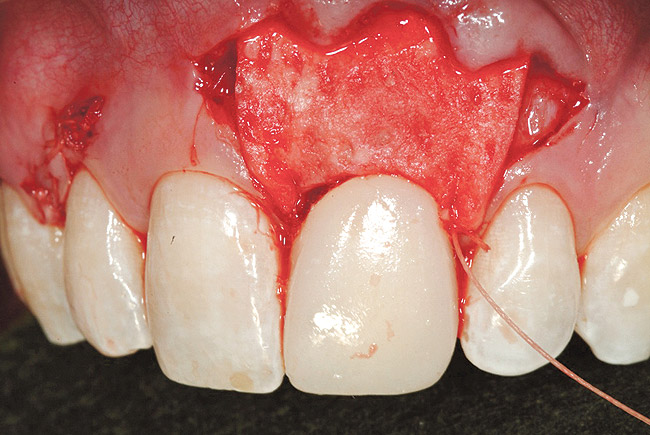

Creation of the facial pouch was accomplished as outlined earlier. Intrasulcular incisions were made from the distal line angle of the right central incisor to the distal line angle of the left canine, with care given to not totally incise the papillae at the interproximal aspect. Using mucoperiosteal elevators and blunt dissection, the pouch was extended apically beyond the mucogingival junction, and laterally to the facial aspect of the tunneled papillae. The pouch was then deepened and mobilized by sharp supraperiosteal dissection. The pre-trimmed acellular dermal matrix (AlloDerm) rehydrated with non-activated PRP, was then placed into the pouch superior to the allogenic bone graft placed to correct the facial defect at the implant site, from the mesial of the right central to the mesial of the left canine (Figure 27). The acellular dermal matrix was then secured with 6.0 polypropylene sutures, and the pouch coronally advanced to cover the dermal matrix graft completely, using 5.0 monocryl sutures by an interrupted sling suturing technique (Figure 28).

Figure 27  Case Three Acellular dermal matrix placed into

Figure 27